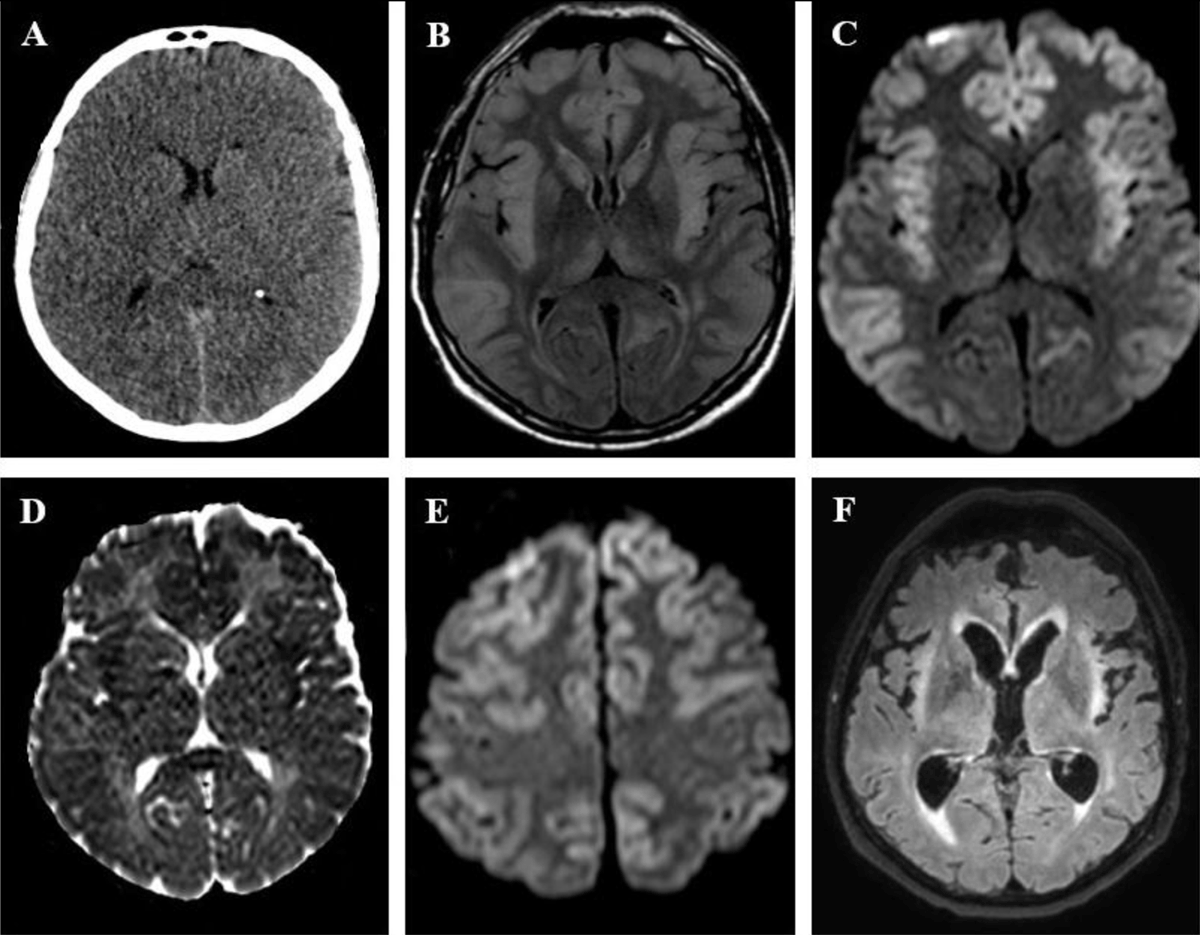

Figure 1

A 56-year-old man presented with status epilepticus and coma four days after bi-pulmonary graft. (A) Non-enhanced CT shows ventricular and sulcal effacement suggesting brain edema. (B) Fluid-attenuated inversion recovery (FLAIR) sequence shows bilateral cortical swelling and high signal, with sparing of the occipital cortex, as well as signal abnormalities in both caudate nuclei and thalami. (C) Diffusion weighted-imaging (DWI; b-value = 1000 s/mm2) and (D) apparent diffusion coefficient (ADC) map show respectively high and low signal of the cortex at the same levels, consistent with cytotoxic edema. (E) DWI sequence at a higher level shows sparing of the peri-rolandic cortex. (F) Follow-up FLAIR imaging at four weeks shows development of atrophy and gliosis in insula bilaterally.